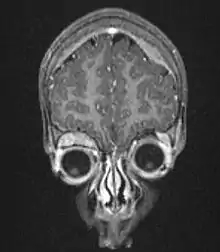

![]() | |

| Microscopic view of a typical neuroblastoma with rosette formation | |

On microscopy, the tumor cells are typically described as small, round and blue, and rosette patterns (Homer Wright pseudorosettes) may be seen. Homer Wright pseudorosettes are tumor cells around the neuropil, not to be confused with a true rosettes, which are tumor cells around an empty lumen.[26] They are also distinct from the pseudorosettes of an ependymoma which consist of tumor cells with glial fibrillary acidic protein (GFAP)–positive processes tapering off toward a blood vessel (thus a combination of the two).[27] A variety of immunohistochemical stains are used by pathologists to distinguish neuroblastomas from histological mimics, such as rhabdomyosarcoma, Ewing's sarcoma, lymphoma and Wilms' tumor.[28]